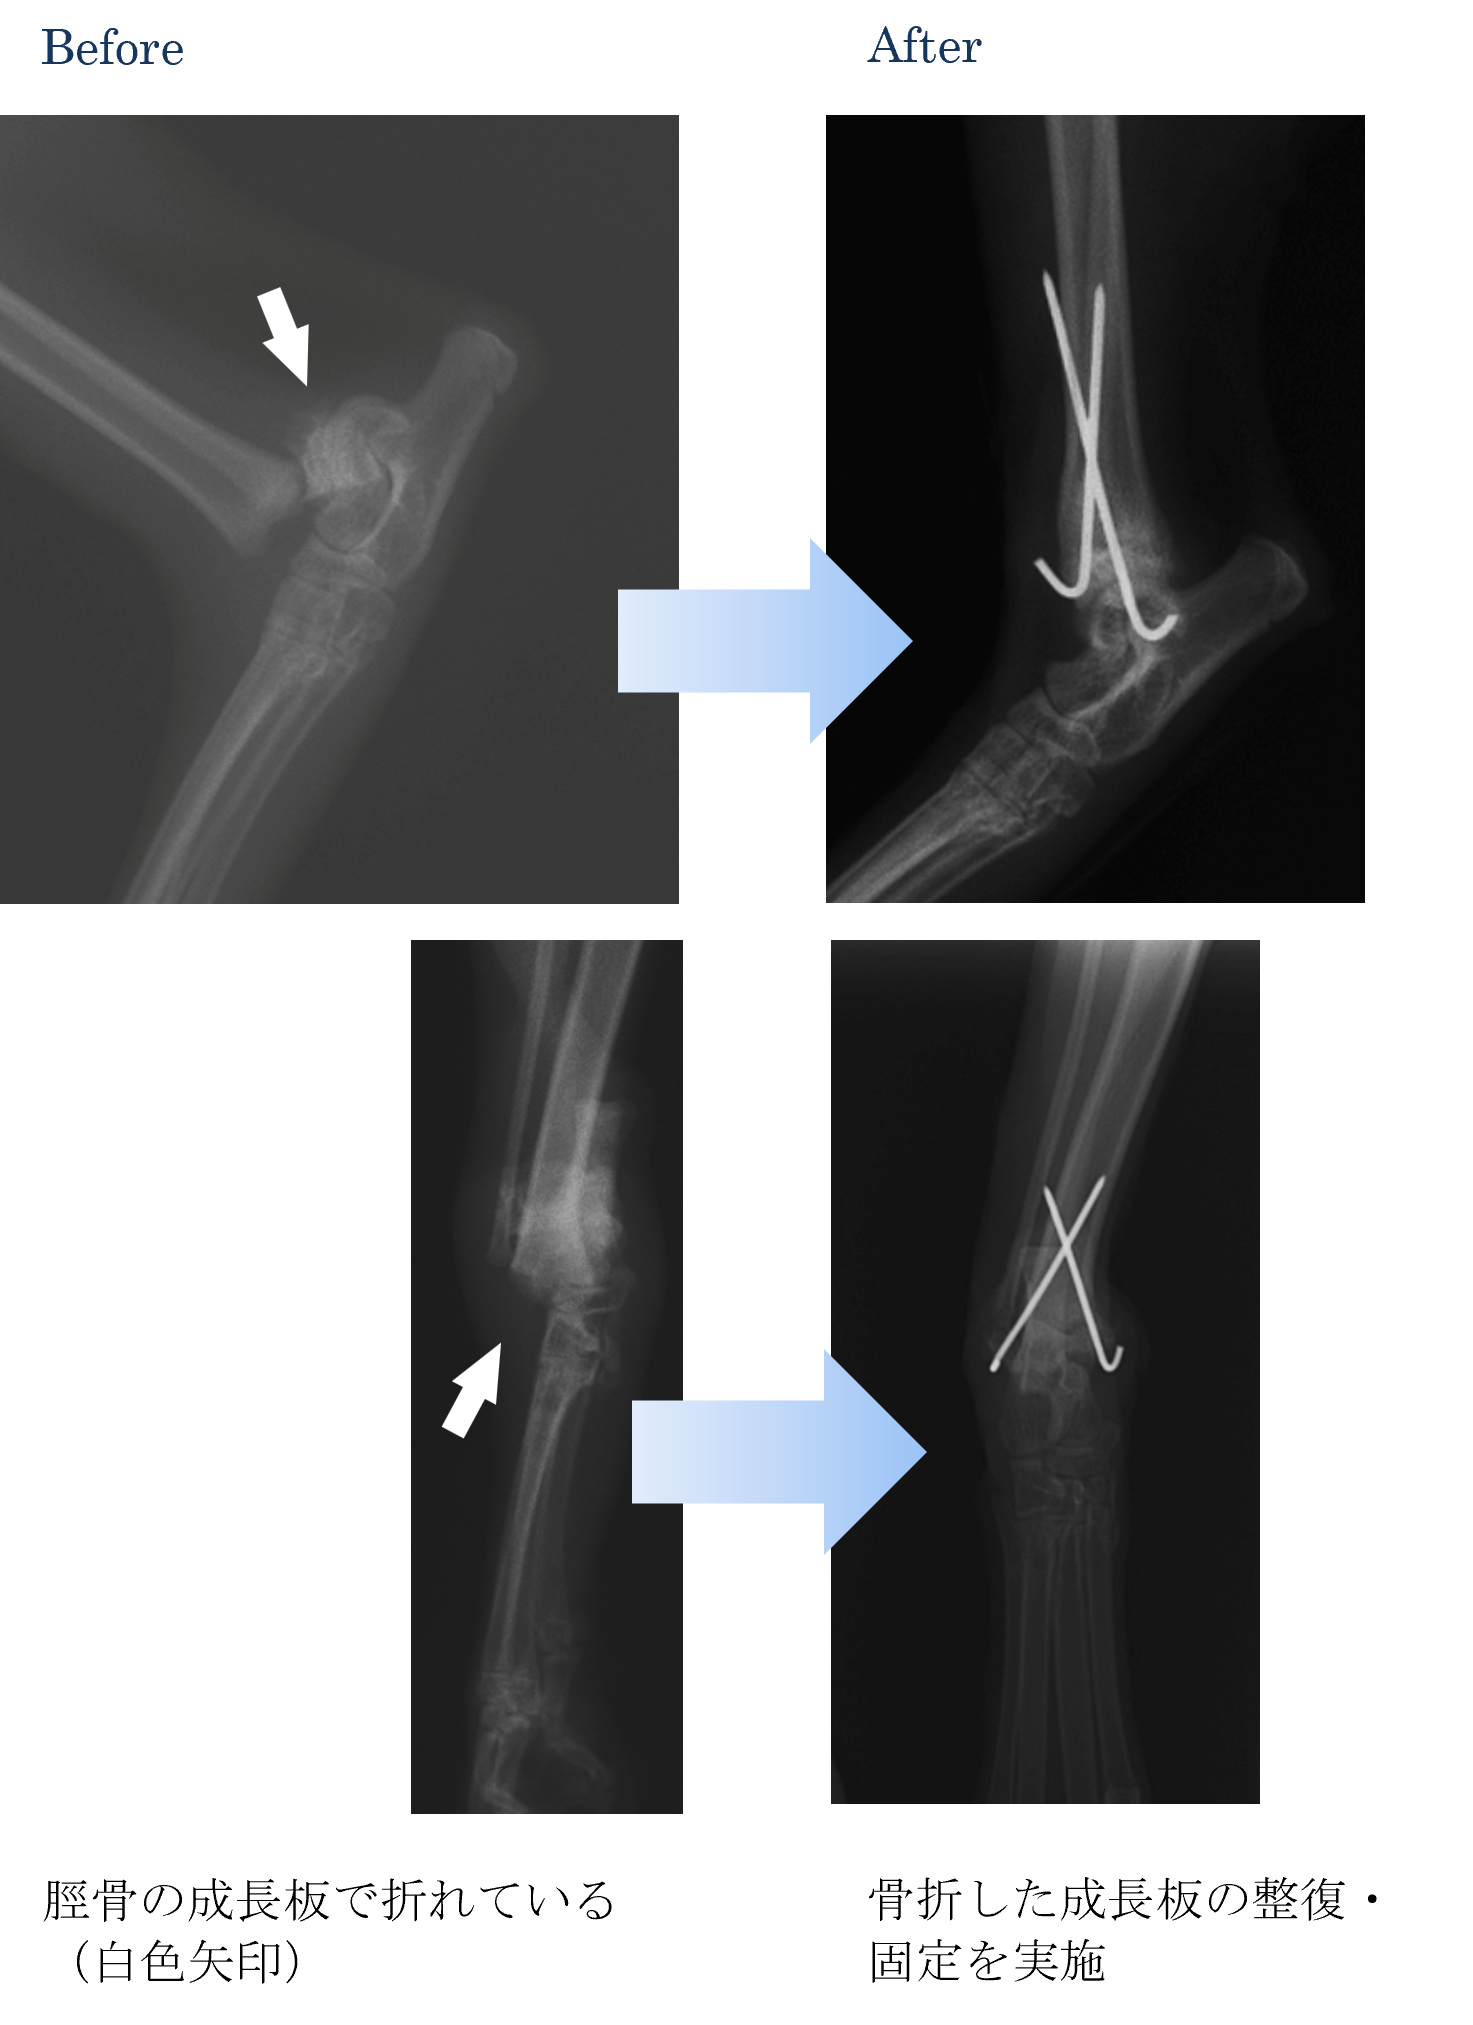

各種検査より、脛骨(すねの骨)遠位成長板の骨折と診断しました。

ご家族と相談して手術で整復して固定を実施することになりました。

骨折部分が癒合したところでピン(金具)を抜去しました。

手術後は以前と同じように走ったり遊んだりすることができるようになりました。